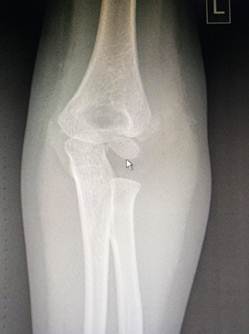

Область локтя в разном возрасте

Василий Оскарович Маркс говорил, что неподготовленный человек на

снимке локтевого сустава здорового ребенка найдёт восемь переломов. Очень даже

может быть – рентгенологическая картина локтя ребенка в возрасте от года до

четырнадцати лет насыщена ядрами окостенения и зонами роста, которые легко

принять за костный отломок или осколок, особенно если в анамнезе есть травма.

1 год - 3 года

В возрасте года выявляется булавовидный метафиз плечевой кости,

ядро окостенения головчатого возвышения и латерального вала блока.

Верхний конец лучевой кости отстоит от уровня щели локтевого сустава

достаточно далеко. Конец локтевой кости находится на уровне суставной щели. К 3

годам на снимках очерчивается основание головки лучевой кости и хорошо видна

блоковидная вырезка локтевой кости с основаниями локтевого и венечного

отростков. В самом конце периода появляется ядро окостенения головки лучевой

кости.

Прямой снимок локтевого сустава ребенка 5 месяцев. Обратите

внимание, насколько далеко отстоят друг от друга видимые,

т.е. окостеневшие части сочленяющихся костей.

Снимок локтевого сустава ребенка в возрасте 1 года. Заметно ядро

окостенения головчатого возвышения и латерального вала блока плечевой кости.